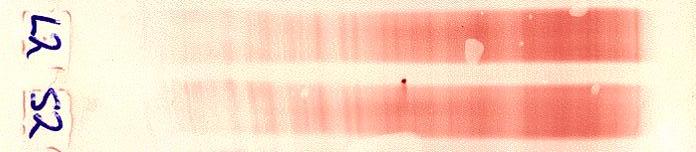

Blot (Immunostaining) negative Type I (IgG-selective staining)

blotnegative